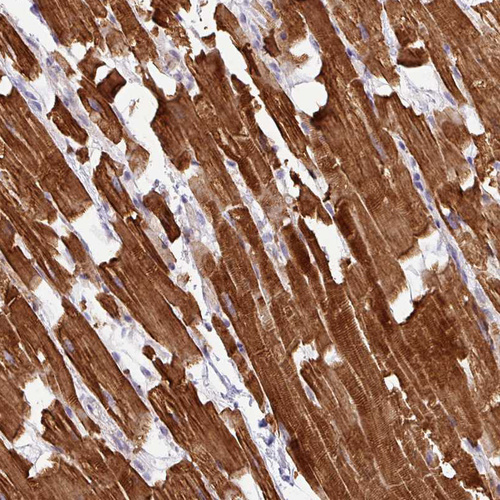

Immunohistochemical staining of human heart muscle shows moderate to strong cytoplasmic positivity in cardiomyocytes.